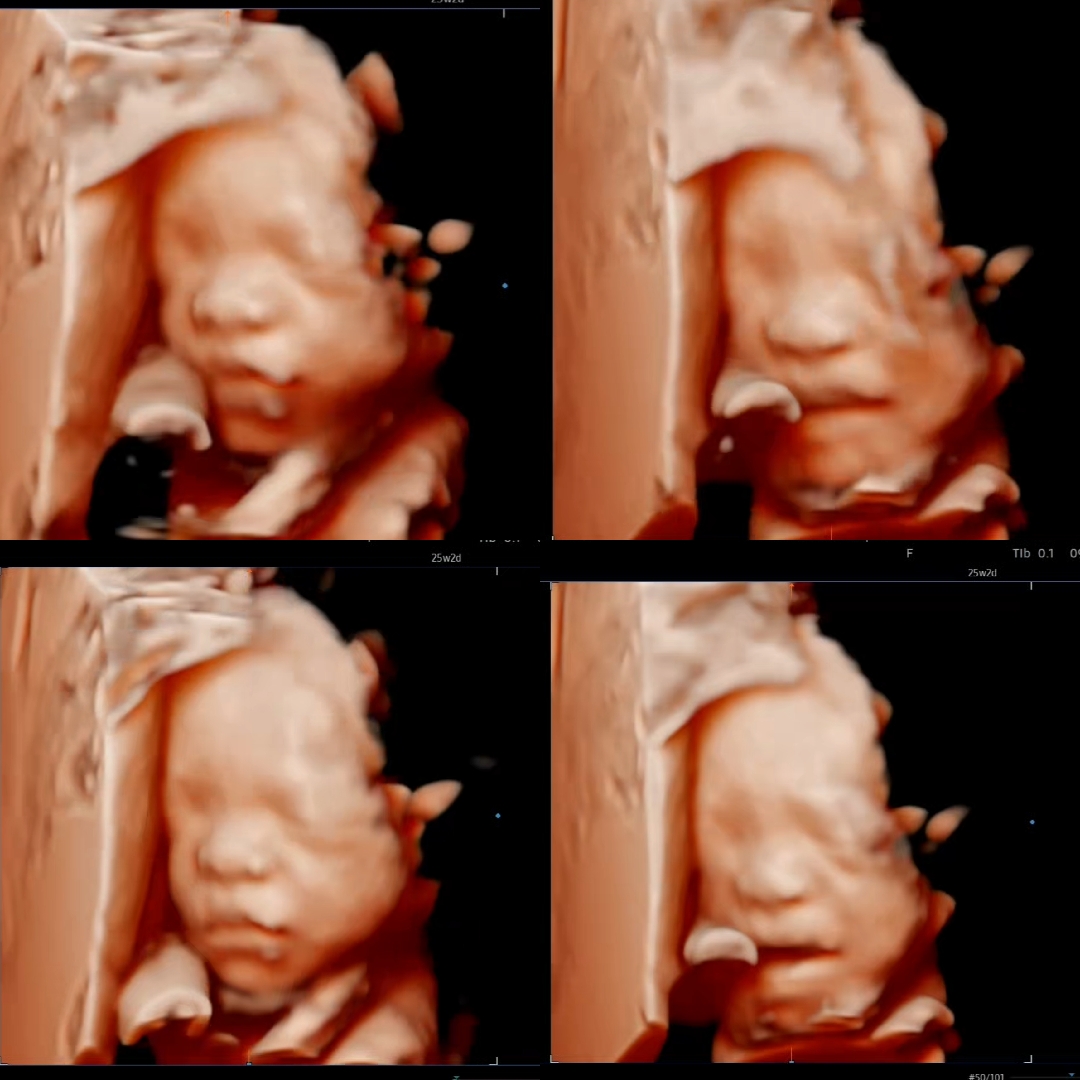

입체초음파 보고왔어요✨️

25주 2일차에 입체초음파 찍고왔어요📷 ✨️제가 다니는 병원은 입체초음파를 25주전에는 안찍어줘서 처음 찍네요~ 배동보니 다른곳은 입체사진으로 팔다리전신 다보이는 하리보같은 사진도 종종 올라와서 신기했었어요~ 남편은 절 똑닮은 아들같다고 좋아하니깐 좋네요ㅎㅎ전 양수도 10센치라 많지 않은편이고, 항상 엎어져서 얼굴을 꽁꽁 숨기길래 기대안했는데 아주 잠시 얼굴을 보여줬네요☺️ 근데 무슨 정신머리였는지 임당검사까지 하려고 금식하고 병원약도 마시며 대기하다가, 입체초음파 보고선 진료보다 순간적으로 끝난거라 생각하고 물을 발칵발칵 마셨네요...가장 중요한 임당검사 체혈을 안하고;; 결국 내일 다시 조퇴내고 병원갑니다. 수고로움+임당검사약 멍청비용까지 지출하고나니 참 어처구니가 없어서... 다 배속에 애가있어서 정신없는탓으로 돌리려구요🤣